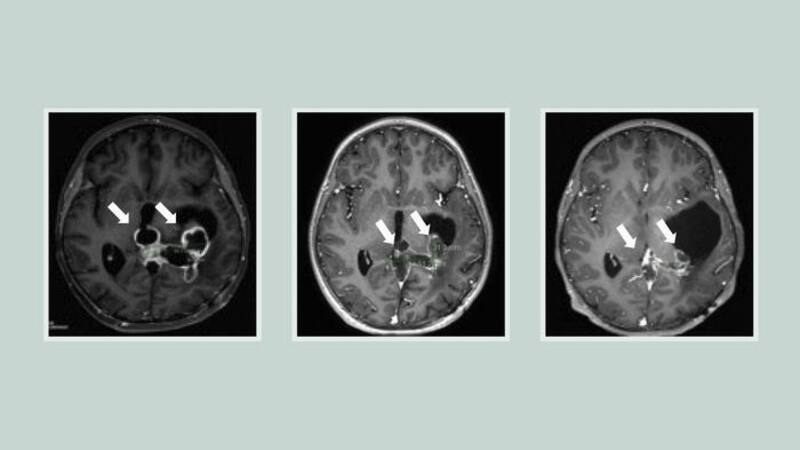

Por primera vez, científicos han encontrado un posible candidato a fármaco que mejoró los resultados de los pacientes con un tipo de tumor cerebral infantil para el que no existen tratamientos efectivos. El compuesto, llamado ONC201, casi duplicó la supervivencia de los pacientes con dos tipos específicos de cáncer cerebral, llamado glioma difuso de la línea media (DMG) o glioma pontino intrínseco difuso (DIPG), en comparación con pacientes anteriores.

Los gliomas difusos de la línea media, incluido el DIPG con una mutación llamada H3K27M, son particularmente agresivos, con una tasa de supervivencia general de 11 a 15 meses. Estos tumores se encuentran con mayor frecuencia en niños y adultos jóvenes. El único tratamiento disponible es la radiación, e incluso eso es difícil ya que los tumores están ubicados en medio de regiones del cerebro con funciones críticas.

En dos ensayos clínicos que probaron ONC201 en un total de 71 pacientes con gliomas difusos de la línea media con mutación H3K27M, la mediana de supervivencia general fue de casi 22 meses para los tumores que no habían recidivado en el momento de la inscripción. Casi un tercio de los pacientes vivieron más de dos años.